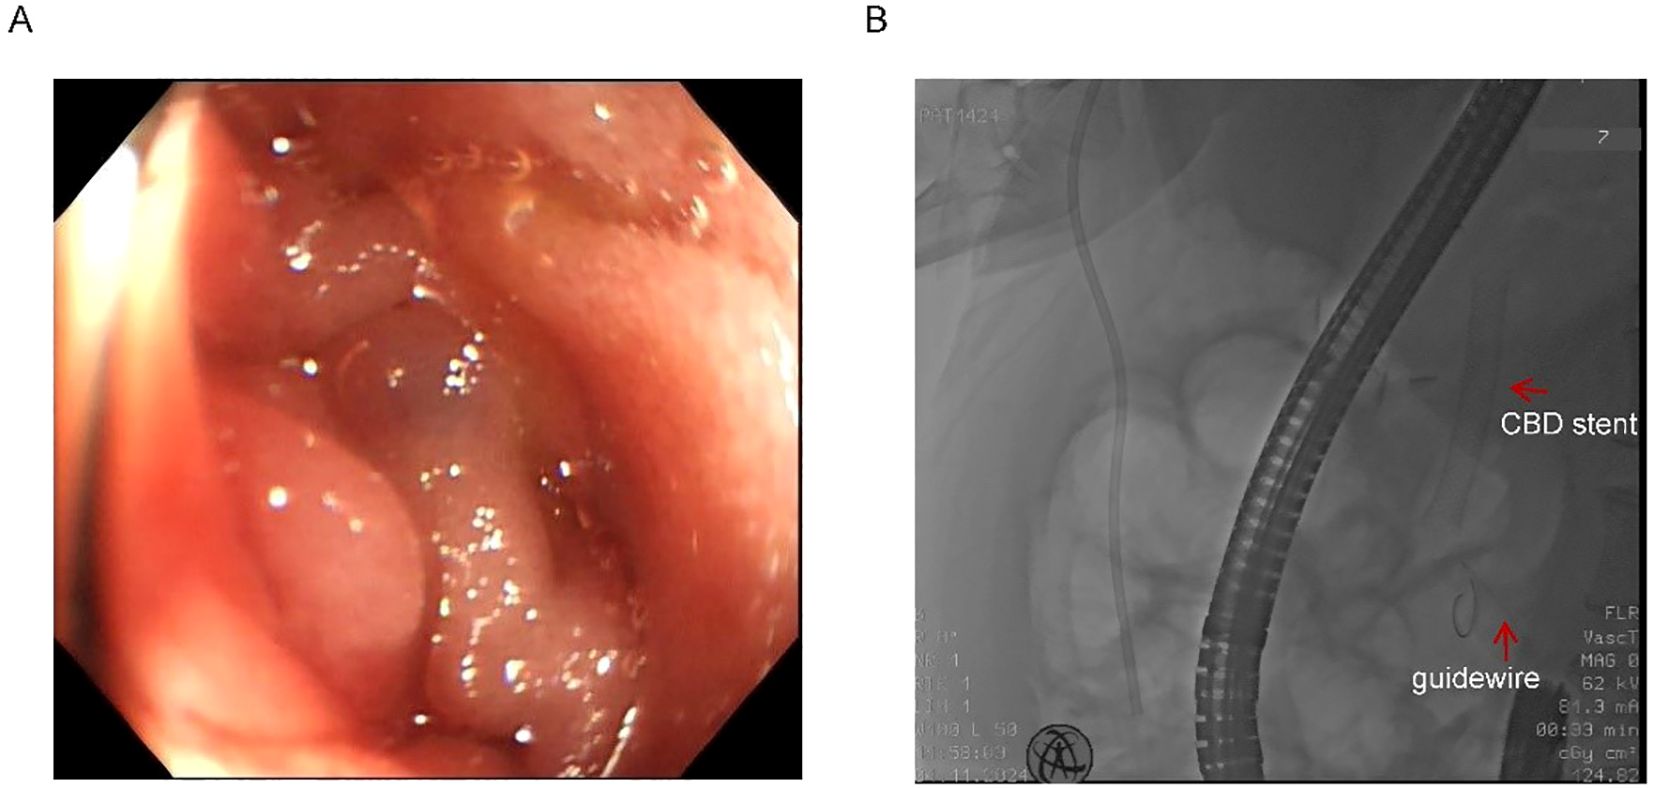

Endoscopic assessment identified a markedly narrowed, angulated afferent limb (Figure 2A). Multiple attempts to navigate a guidewire through the stricture via conventional endoscopy were unsuccessful due to compression and twisting of the afferent loop (Figure 2B). Given the patient’s severe infection and the distal location of the afferent loop obstruction, surgical intervention under general anesthesia was considered high-risk and therefore not feasible.

Panel A shows an endoscopic image of the inside of the digestive tract, with smooth, pinkish tissue. Panel B displays an X-ray image highlighting a common bile duct (CBD) stent and a guidewire, marked with arrows and labels.

Figure 2. Twisted afferent loop and failed guidewire passage. (A) Endoscopic view of the extremely narrow and twisted afferent loop. (B) Failed attempts to pass the guidewire through the stricture. Red arrows indicate the previously placed CBD stent and the guidewire.